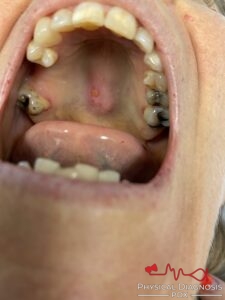

This patient demonstrates tongue findings in hereditary hemorrhagic telangiectasia

Patient 3: